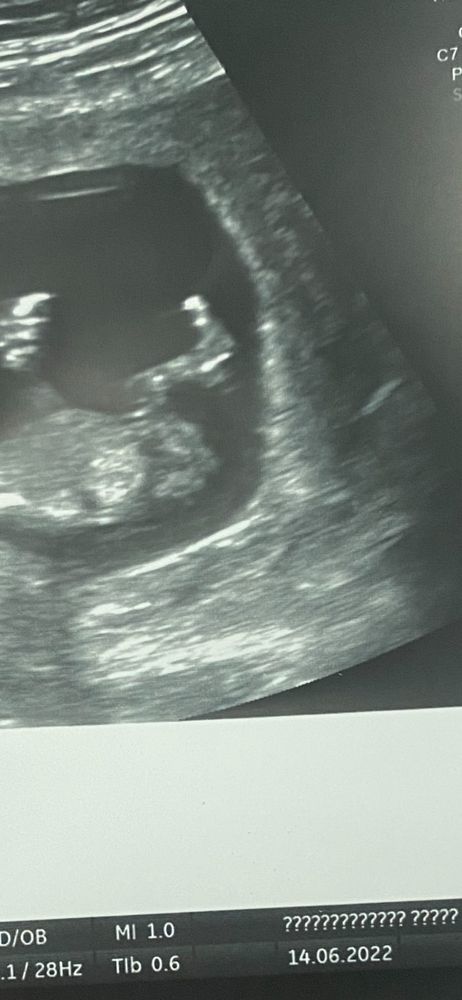

Обновила фото

с гендер пати )

01.07.2022

Евгения ,

как и обещала отписываюсь

у нас девочка 👧🏼 😭😭🥲 я просто не верю все были правы ! Вы просто лучшие тут девочки как вы так увидели